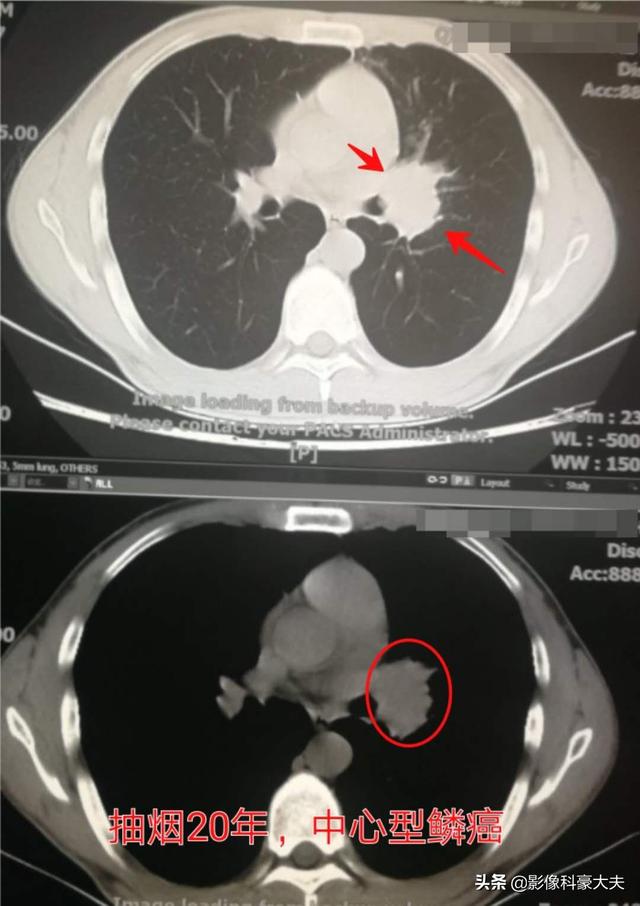

Ce patient âgé d'un peu plus de 30 ans, fumeur depuis 20 ans, s'est vu diagnostiquer un cancer squameux central du poumon il y a deux ans en raison d'une toux récurrente et de la présence occasionnelle de sang dans les expectorations. Il n'a pas été revu depuis et n'est pas sûr d'être encore en vie. S'il n'avait pas appris à fumer à l'adolescence, il n'aurait pas développé de cancer du poumon si jeune.